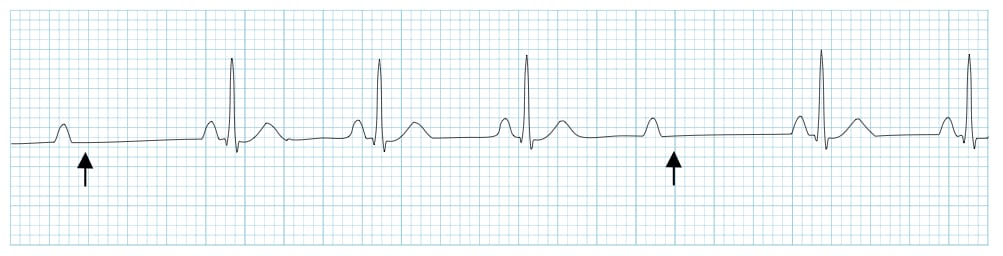

2nd degree AV block, Mobitz type 1 (Wenckebach) #

• في هذا النوع تلاحظ زيادة تدريجية في مسافة PQ الى ان تأتي موجة P لا تليها QRS .

• يتتالى هذا النمط بعد ذلك بنفس التسلسل ، بمعنى آخر تزايد تدريجي في مسافة PQ حتى تأتي P بدون اي QRS بعدها و بعد ذلك يعود التسلسل لمسافة PQ قصيرة يليها زيادة تدريجية في مسافة PQ و هلم جرا.

• المسافة ما بين ال P-P تكون متساوية نسبيا.

• هذا النوع مثل النوع الاول من AV Block يعتبر حميدا في غياب الاعراض. قد يلاحظ بعض الاحيان في بعض الرياضيين و المرضى الذين يتداوون بحبوب Beta blockers.

2nd degree AV block, Mobitz type 1 (Wenckebach)